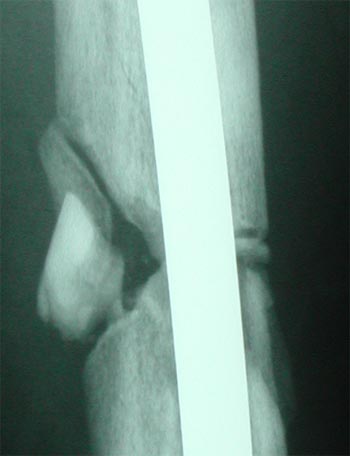

X-Rays Of My Broken Femur - Lateral Closeup

Week 21